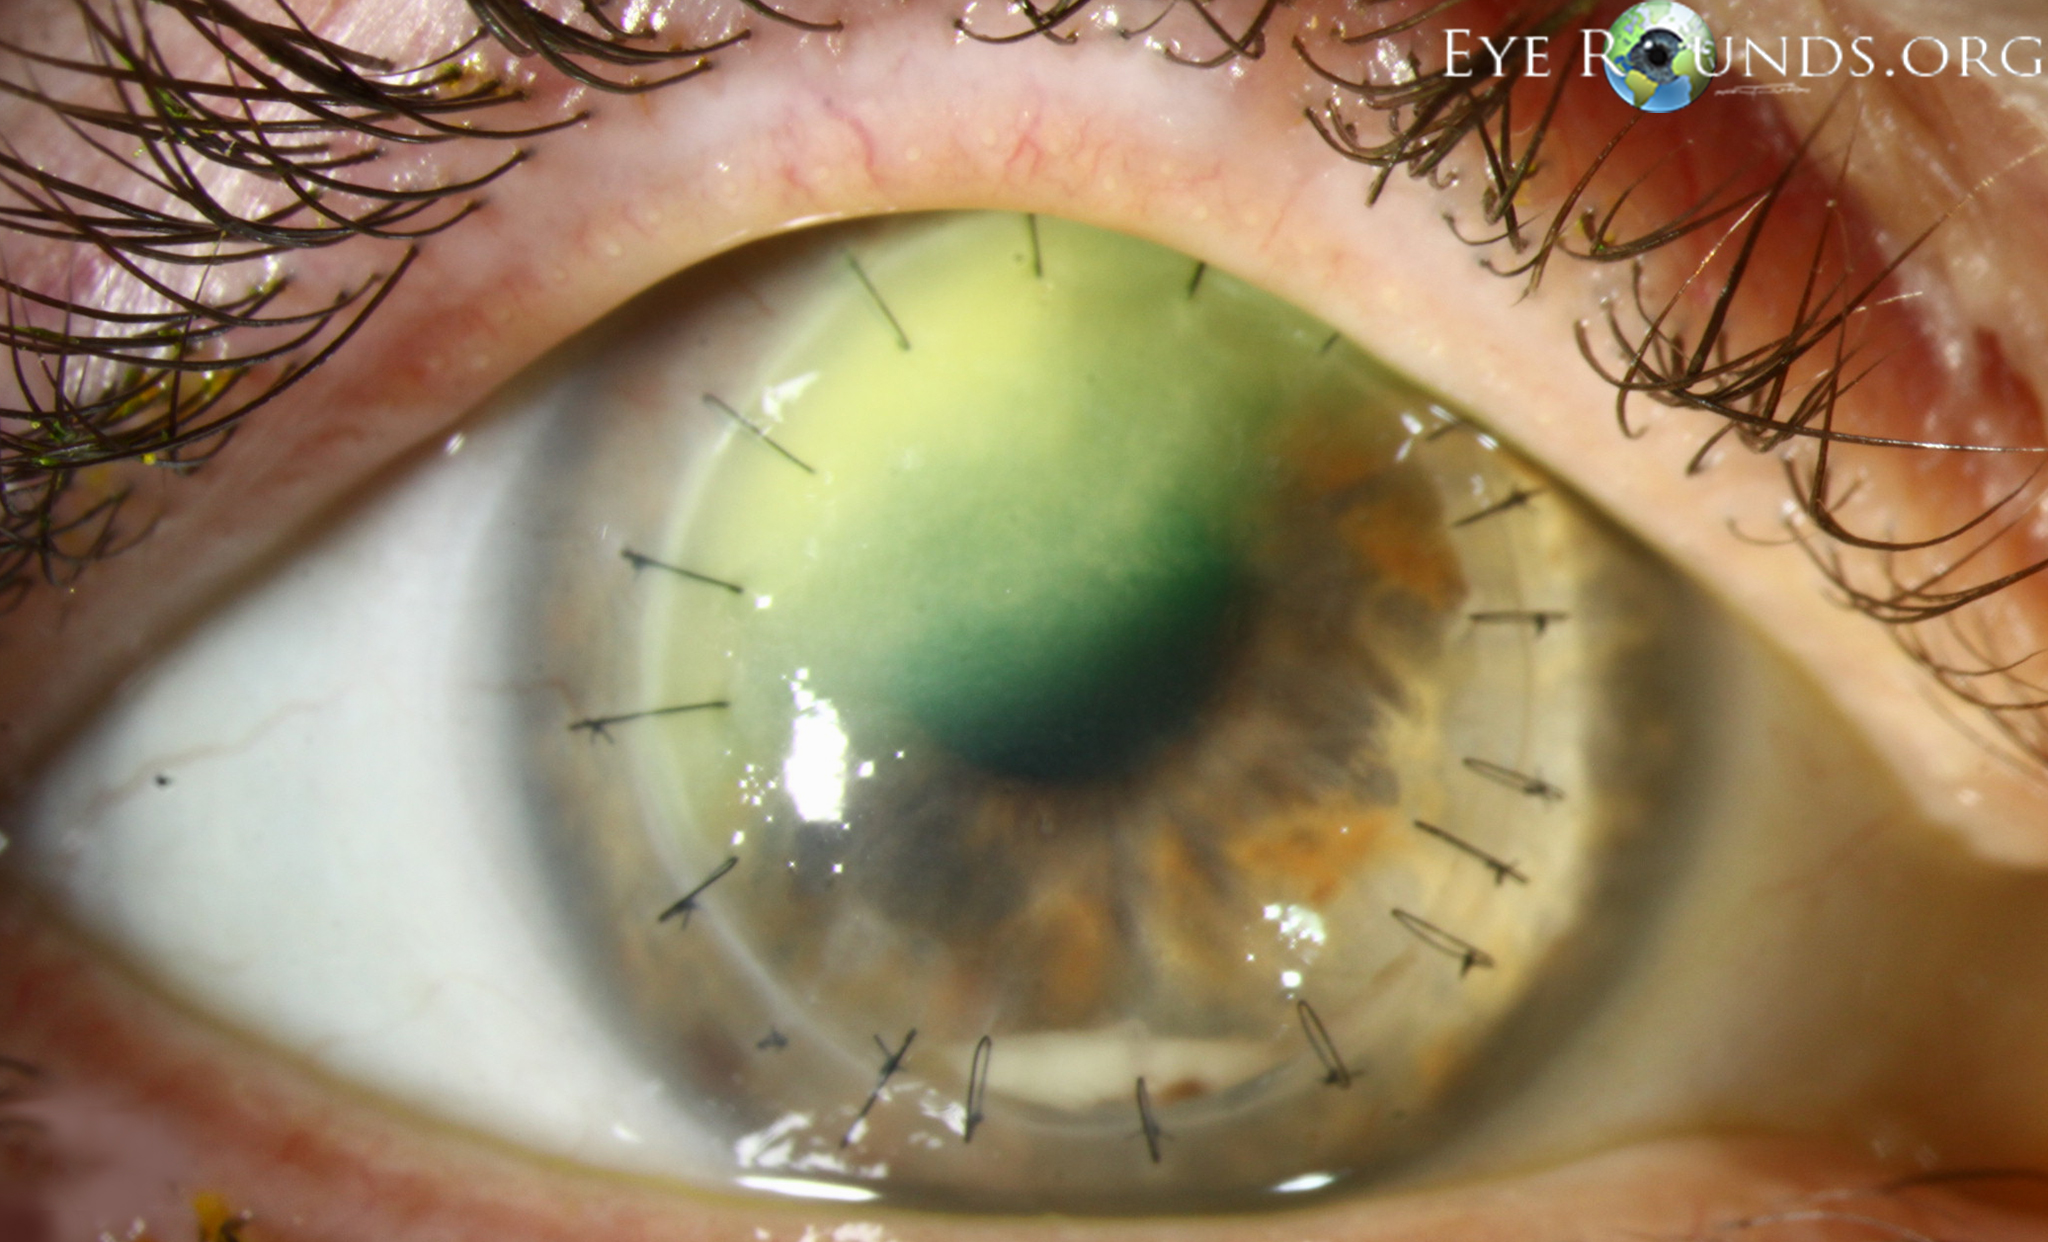

Fungal keratitis is much less common than bacterial keratitis in the United States. Risk factors for developing fungal keratitis include trauma with vegetable matter, immunosuppression (especially with topical corticosteroids), and contact lens wear. The classic appearance of fungal keratitis is a gray-white, dry-appearing infiltrate with feathery borders. However, these findings are not always present, nor are they pathognomonic for the disease, so corneal cultures, smears, and scrapings are often utilized to aid in the diagnosis.

In addition to these traditional detection methods, in vivo confocal microscopy has proven to be an advantageous tool in the timely diagnosis of fungal keratitis. By providing the ability to directly visualize the presence of fungal-like structures throughout the entire depth of the cornea, confocal microscopy allows for a more rapid detection of fungi. Additionally, given the noninvasive nature of confocal microscopy, it can be used repeatedly over time to monitor response to treatment based upon the density of fungi.[1]